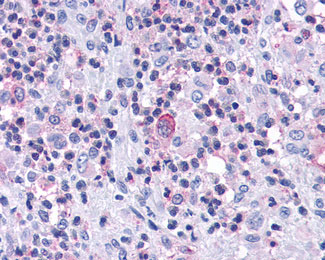

Anti-CCR7 antibody IHC of human Bone, Eosinophilic Granuloma.

Anti-CCR7 antibody APR15286G IHC of human lymph node. |